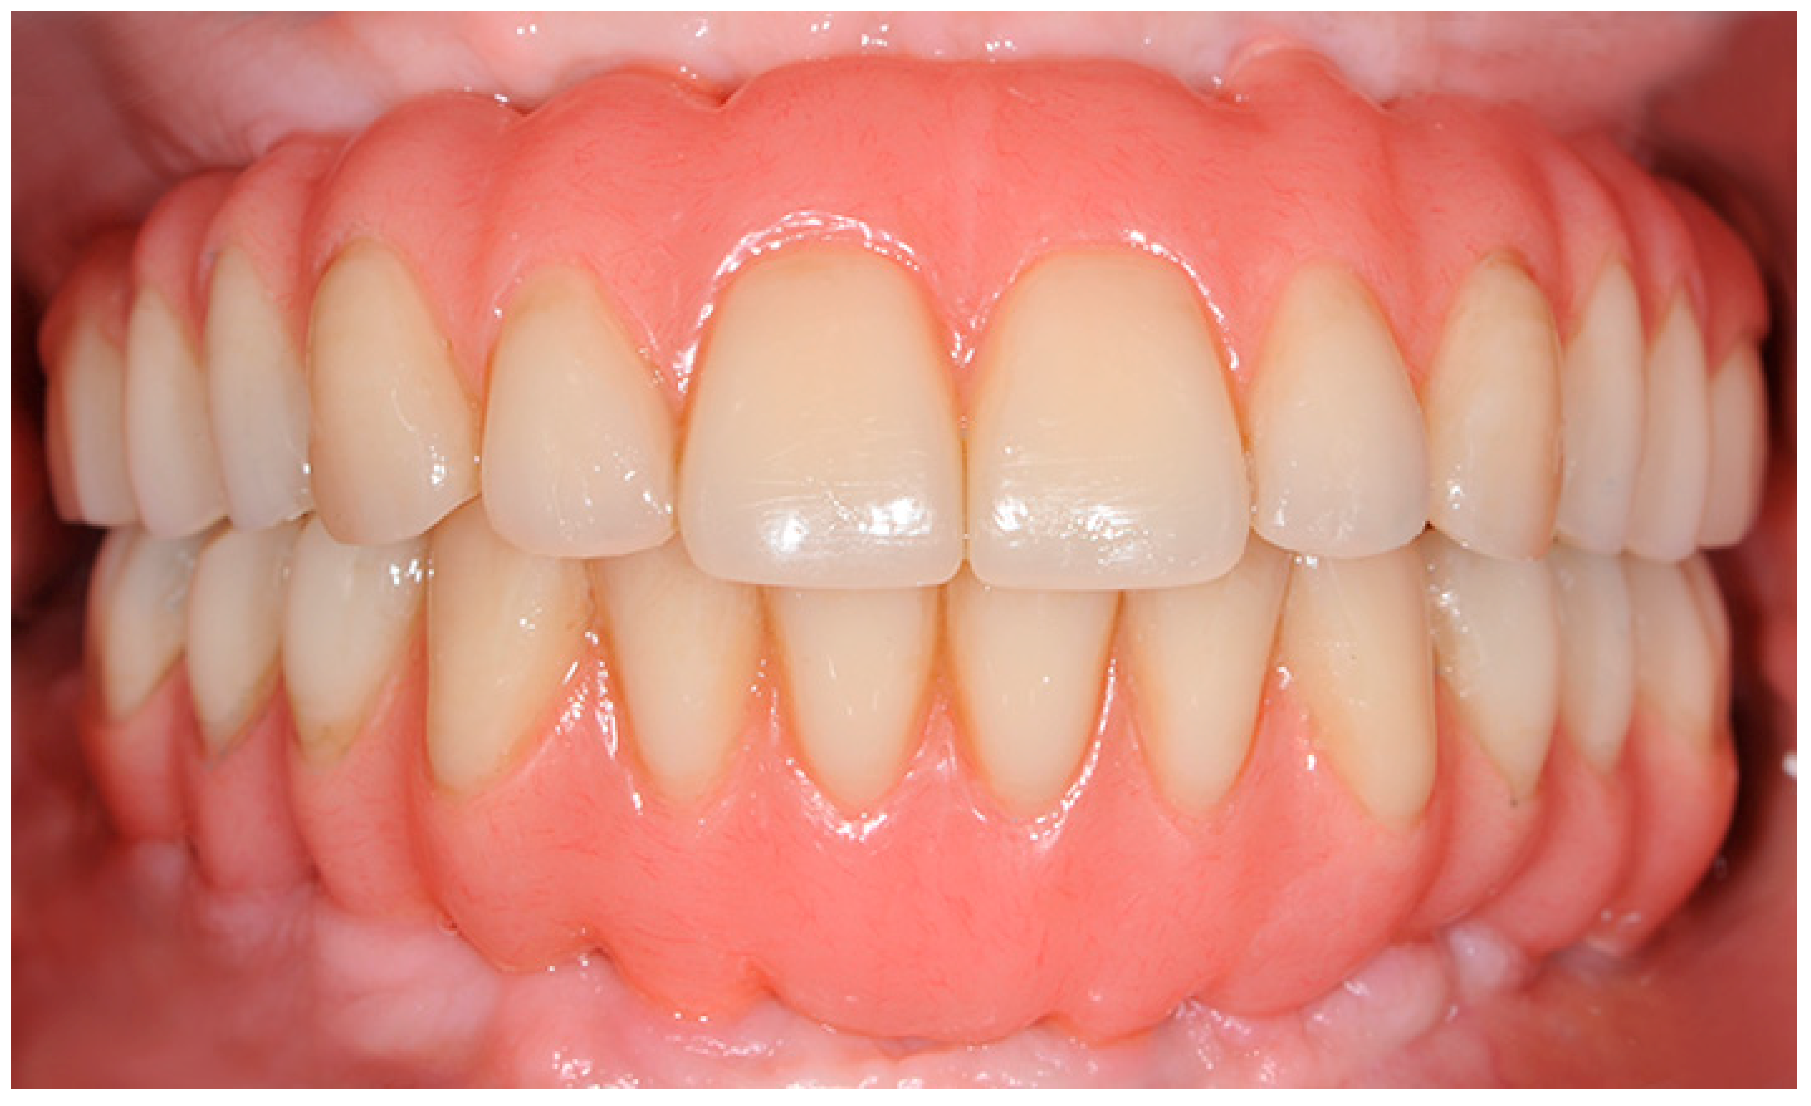

After 6–8 months, the six immediate provisional implants were removed, and a new full-arch screw-retained temporary prosthesis was delivered. After soft tissue maturation, the definitive prosthetic rehabilitation was performed (Figure 4).

Figure 4. Definitive prosthetic rehabilitation.